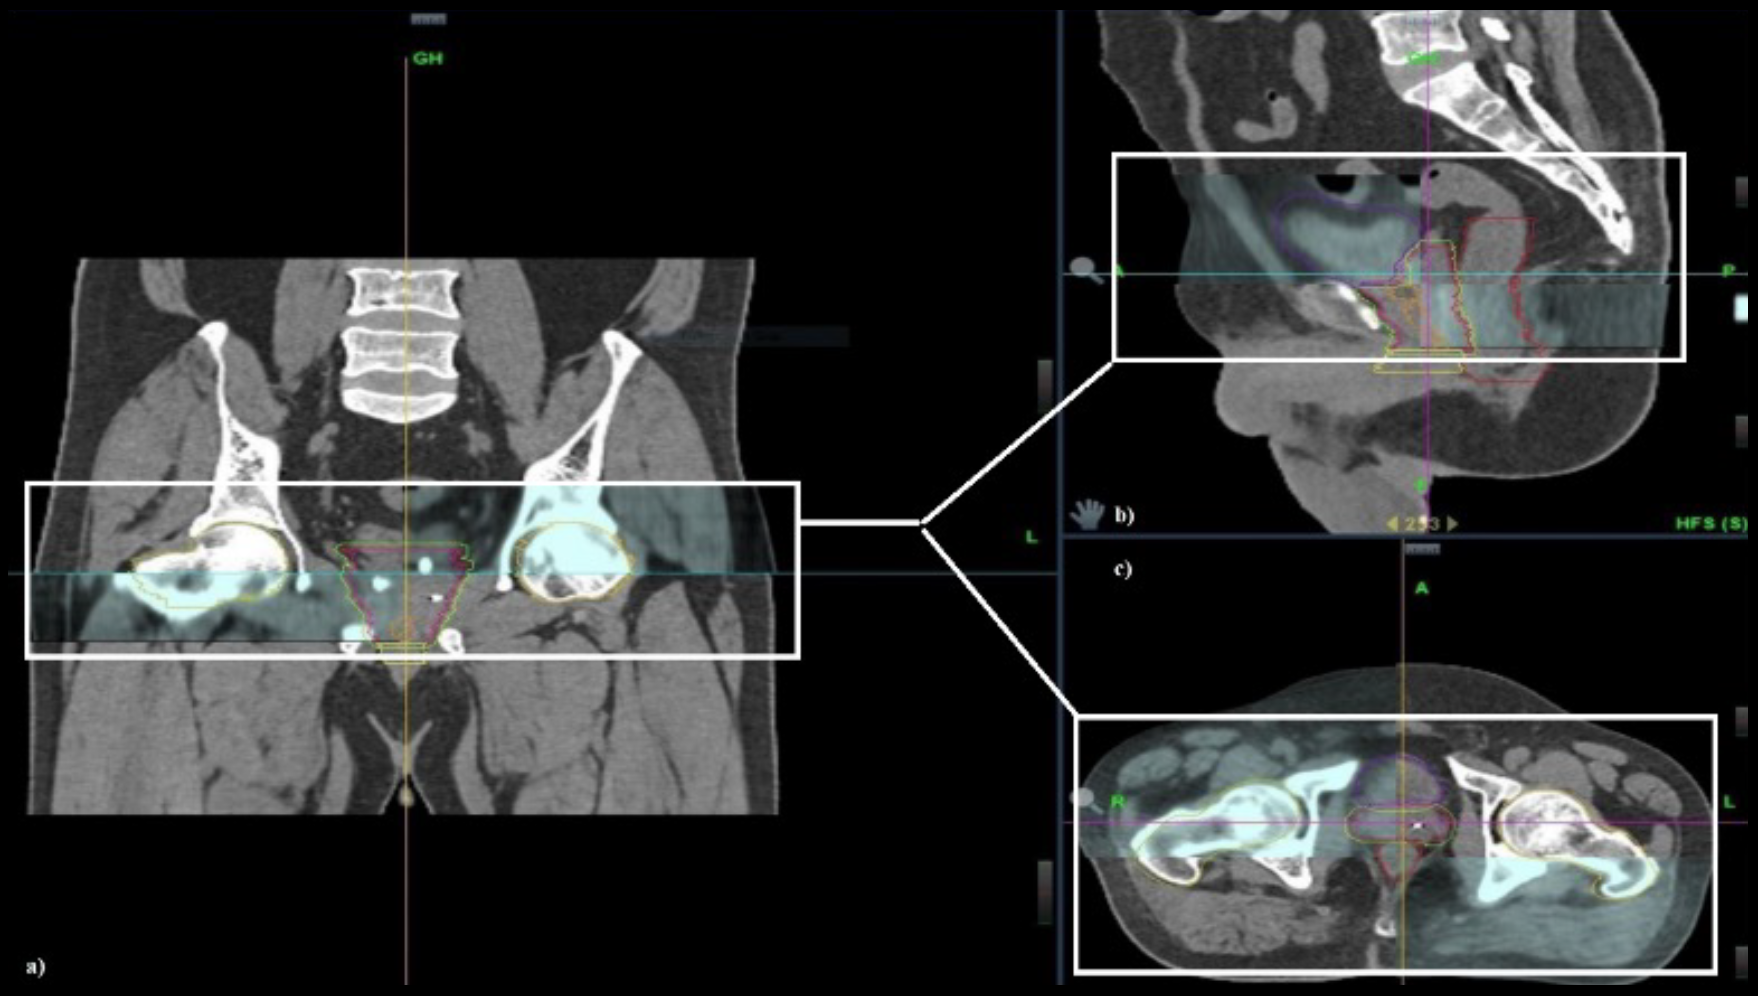

This retrospective study examines cancer control and health-related quality of life (HRQOL) outcomes in high-risk prostate cancer patients receiving robotic stereotactic body radiation therapy (SBRT) with Synchrony® real-time adaptive motion management.